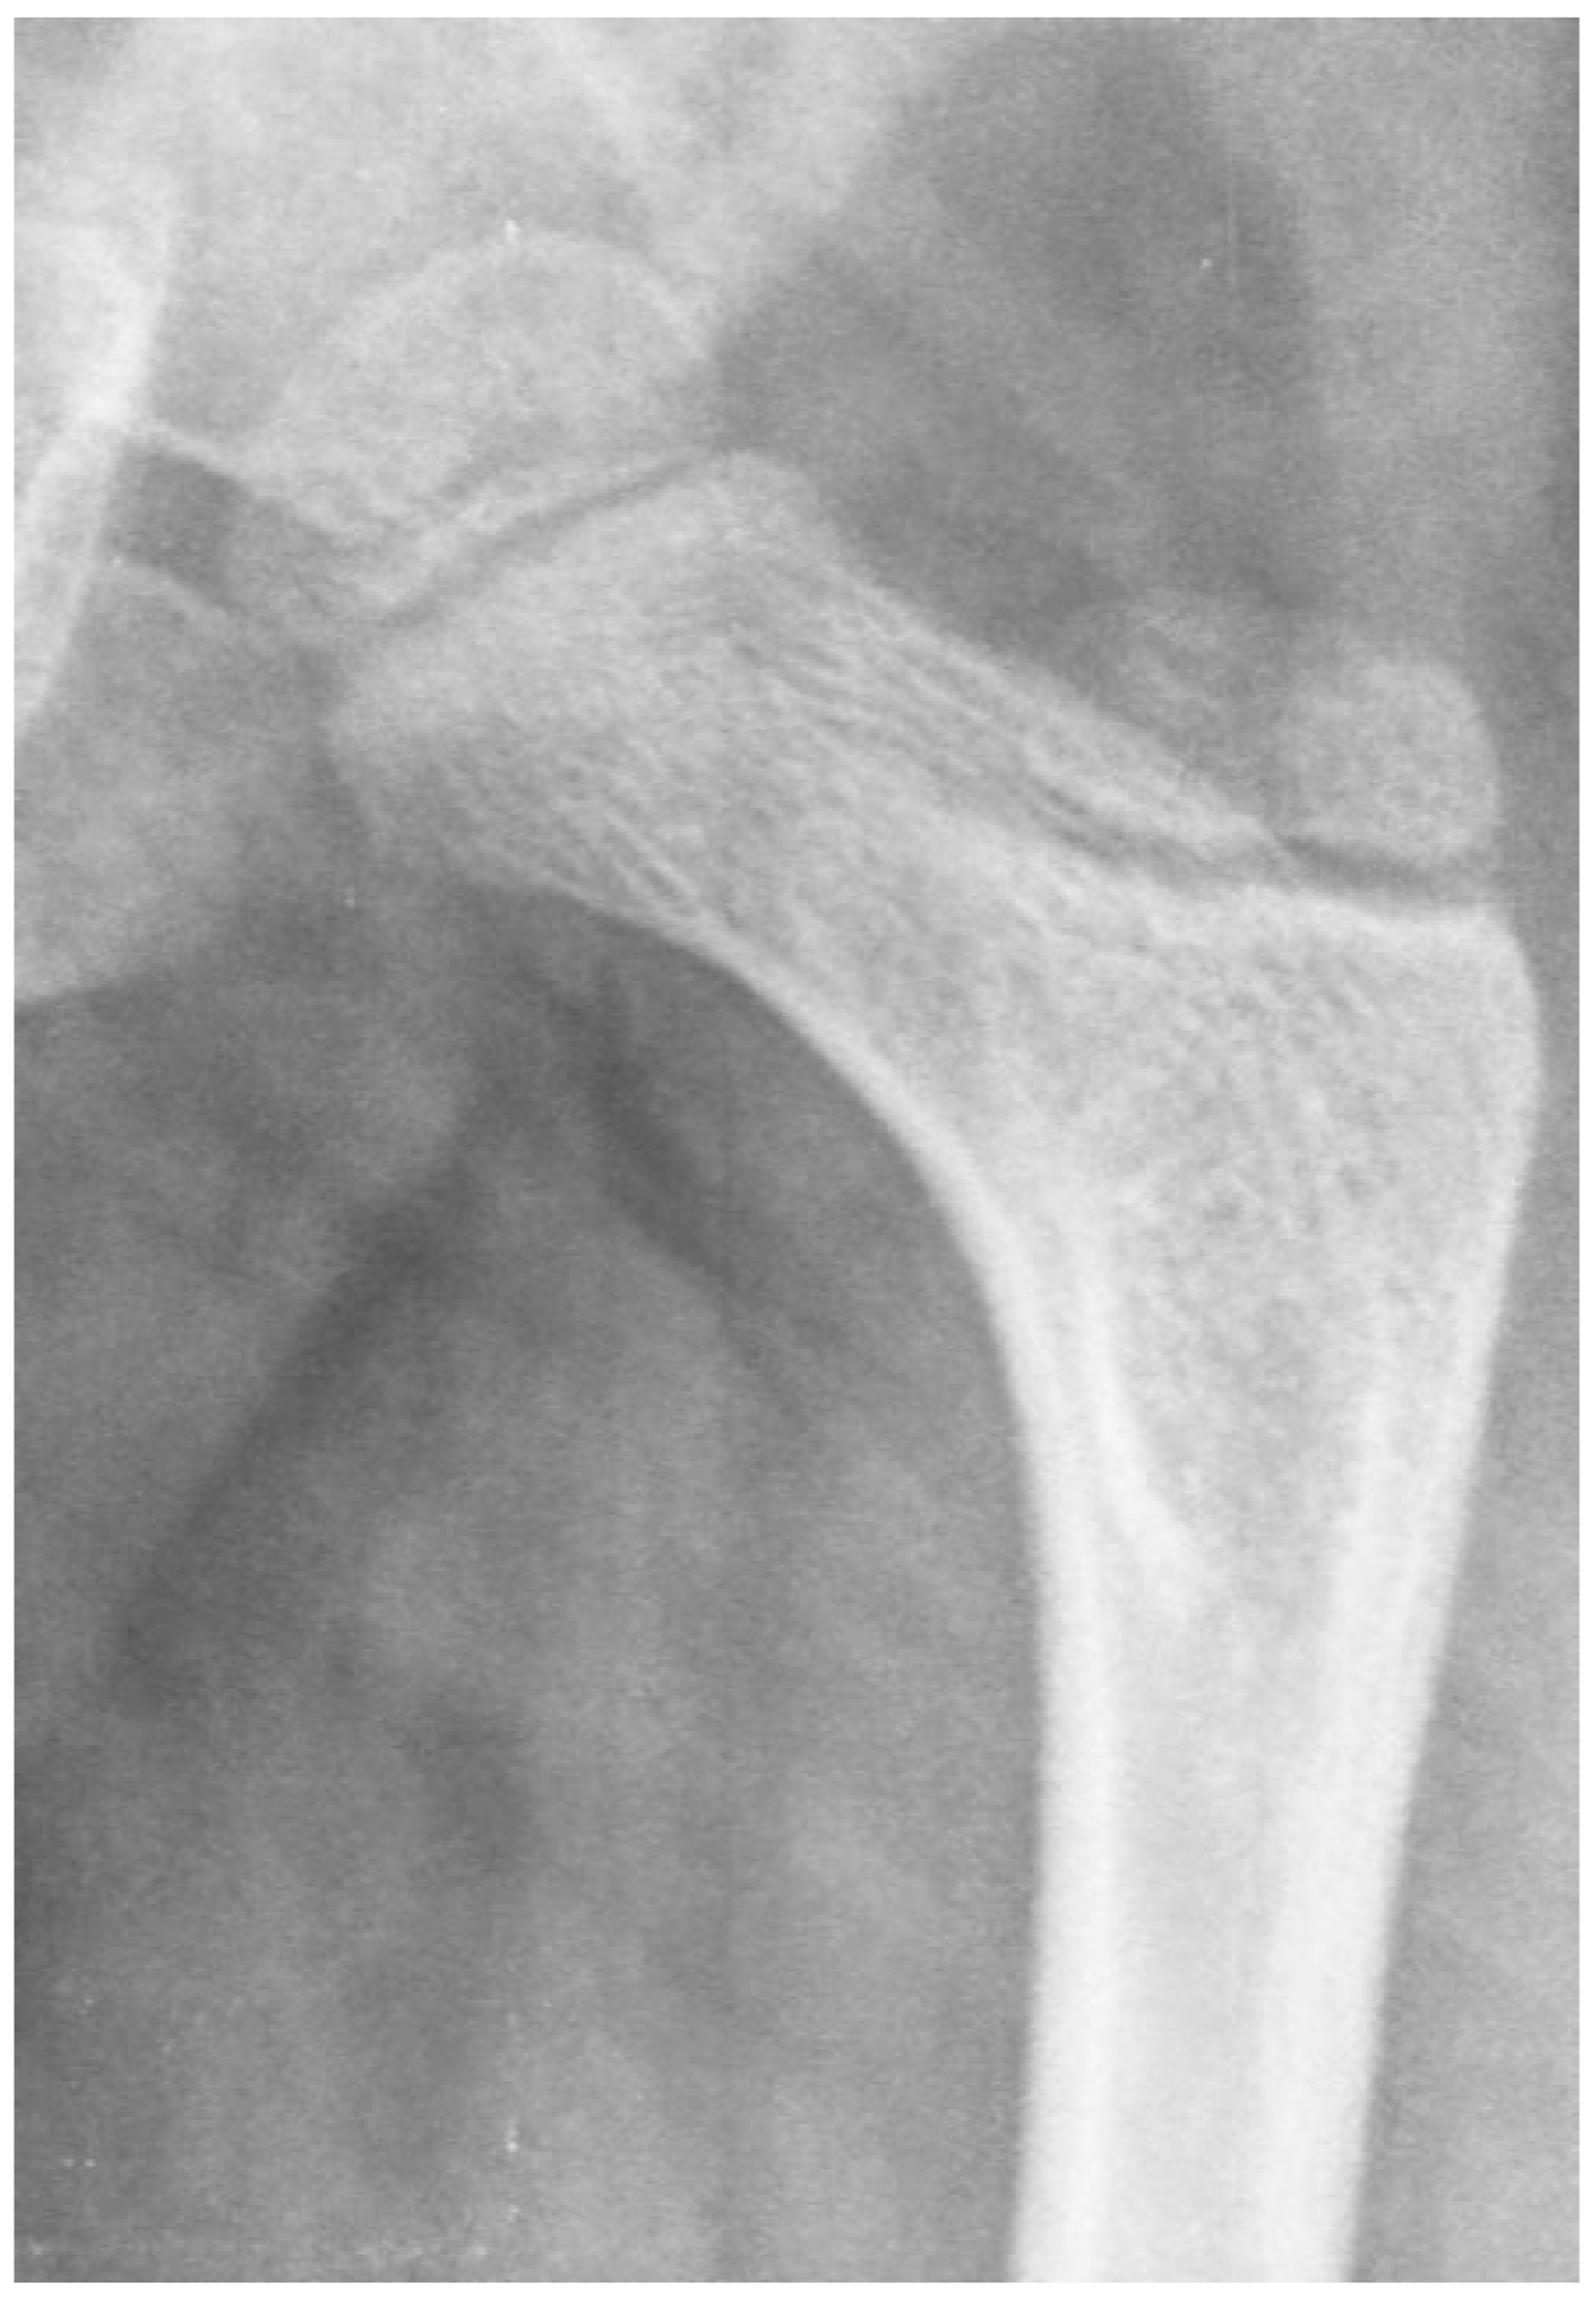

3.4. Femoral Factors Influencing Hip Pathology

3.4.1. Pathologic Role of Femoral Anteversion

3.4.2. Pathologic Role of Coxa Valga and the Impact of its Correction on Spastic Hips